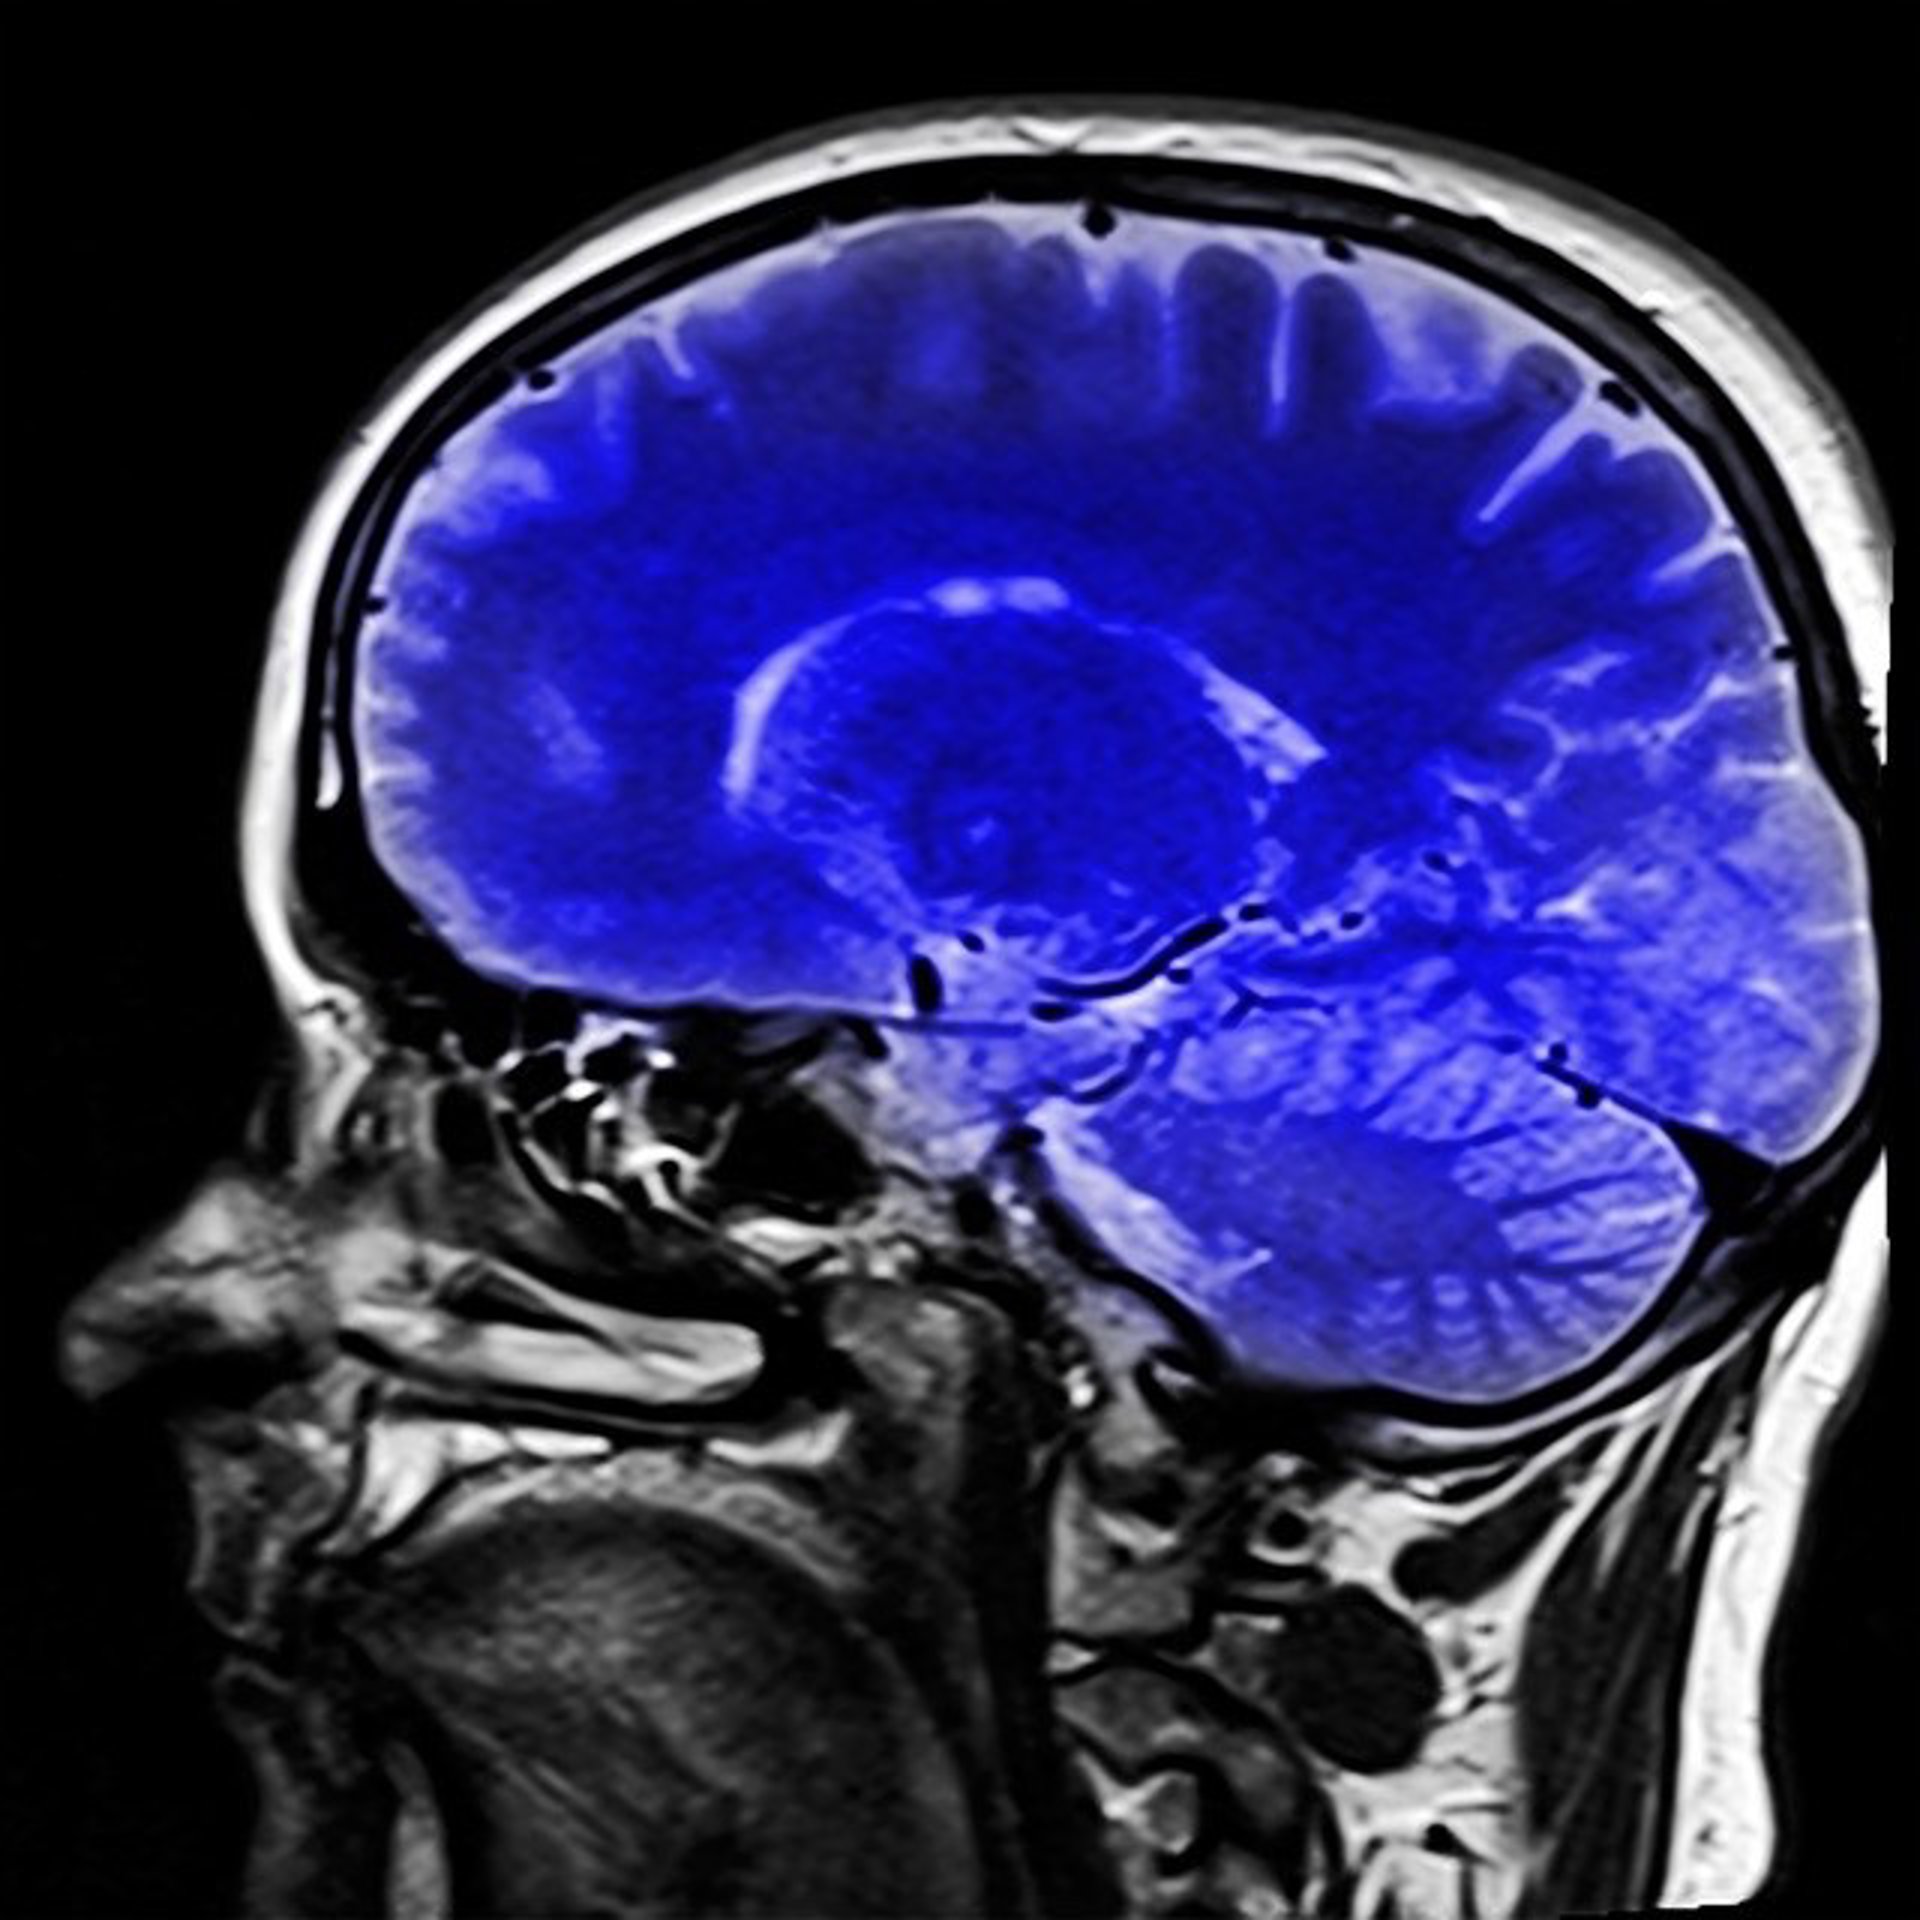

Resonancia magnética del cerebro

PIXABAY - Archivo